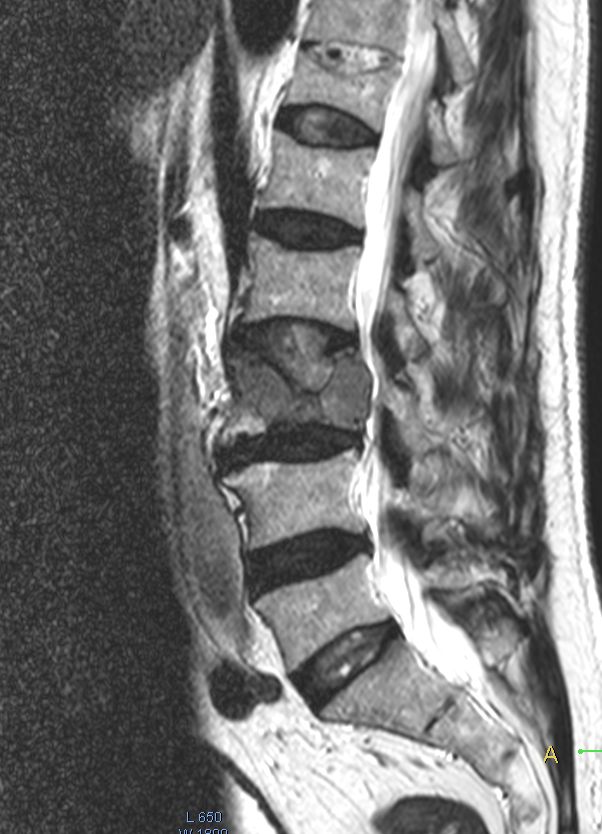

75-jähriger Mann mit Rückenschmerzen seit 5 Monaten.

Ausstrahlung in den rechten Oberschenkel. Solitäres Plasmozytom.![]() | |||